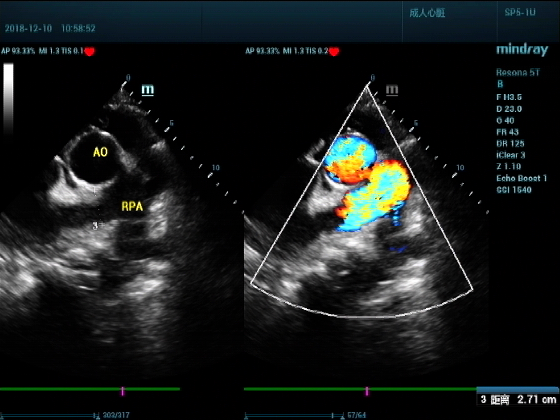

超声可见:左房,右房,右室明显增大,主肺动脉及右肺动脉增宽,二尖瓣中度反流,三尖瓣重度反流,肺动脉轻度高压,心律不齐

心包积液盆腔积液。淤血性肝增大,肝静脉增宽。(右心衰声像改变)